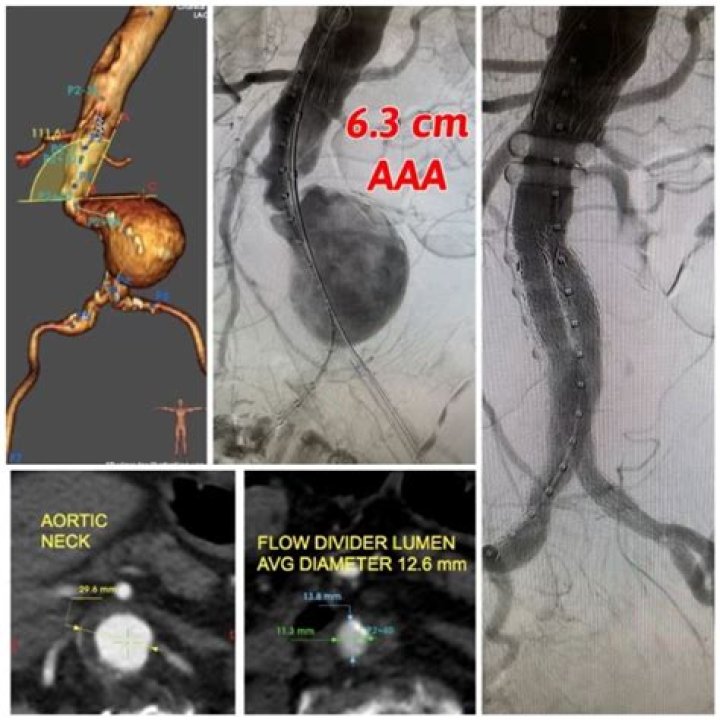

Dr. Muzammil Musani, MD – Fort Wayne, IN